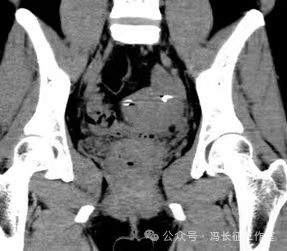

冠状位CT重建图显示宫底2侧的弹簧圈

微信图片_20240223171515(8).jpg